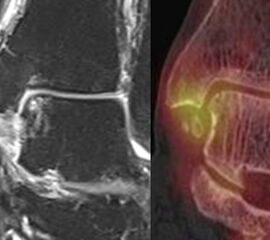

Mit der SPECT/CT können symptomatische Band-Läsionen des Sprunggelenks und der Fußwurzel eindeutig nachgewiesen werden, wie eine Fallsammlung in Korrelation mit MRT-Befunden von 2019 eindrucksvoll zeigt und was zunächst etwas verwundert. Der SPECT/CT-Befunder muss dabei jedoch gute Kenntnisse der Bandanatomie haben, um diese Befunde richtig zuordnen zu können. Je nach Lokalisation der Sehnenläsion bzw. der Tendinopathie findet sich eine Anreicherung des Tracers im Bandverlauf 11.

Ein solche Situation wird beispielhaft in Abbildung 8.7. a bis d gezeigt. Der Patient erlitt eine OSG-Distorsion rechts vor 5 Monaten mit persistierenden Beschwerden postero-medial. Bekanntes prominentes Os trigonum. Anamnestisch Z. n. früheren Sprunggelenksdistorsionen bei regelmäßigem Fußballspiel. Z. n. Außenbandruptur. Die SPECT/CT erfolgte nachdem ein MRT 8 Wochen zuvor verschiedenste Befunde von unklarer Relevanz gezeigt hatte (....dehiszent stehendes Os trigonum mit umgebenden Erguss, kleine Exostose und subchondrale Zyste am Innenknöchel posterior am Ansatz des Retinaculum der Tibialis-posterior-Sehne ohne Hinweis auf eine Retinaculumruptur oder Sehnen-Dislokation. Ödematöse Veränderungen der Bänder am Sinus tarsi, im Ligamentum fibulocalcaneare, fibulotalare anterius und Deltaband Pars tibiotalare….). Nur die SPECT/CT zeigte einen fokalen eindeutigen Befund: eine aktivierte Stressreaktion im Bereich der Pars tibiotalaris posterior des rechten Deltabandes. Kein Nachweis eines aktivierten Os trigonum.

Eine Erklärung für diese Beobachtungen liefert die Pathophysiologie der Tendinopathie. Eine Tendinopathie infolge eines Traumas oder mechanischen Stresses führt zur Freisetzung von zahlreichen verschiedenen Gewebsfaktoren (zum Beispiel: TNF-alpha, IGF-II, IGFBP5, PG-R1, LTBP3, TGF-ß1, Neutrophile Elastase, SAA4, Protein S100-A9, PG-H2-D-Isomerase, BMP (bone morphogenic protein), Hedgehog, Wnt, Hypoxia-inducible-factor-1-alpha), die zu einer Stimulation von Sehnen-Stammzellen bzw. Gewebs-ständigen Progenitor Zellen führen. In Abhängigkeit des Mikromileus tritt eine Chondrogene / Osteogene Fehl-Differenzierung der Zellen ein; ein aktiver Prozess, der mit dem szintigraphischen Tracer sichtbar gemacht werden kann 68. Dieser pathophysiolgische Prozess erklärt die bei älteren Bandläsionen häufig nachweisbaren Verkalkungen im Bandverlauf bzw. an der Band-Insertion. In der Phase, in der noch keine radiologischen makroskopischen Verkalkungen zu sehen sind, ist die Aktivität der o. g. Osteoblasten, die sich aus Sehnen-Stammzellen fehl differenziert haben gesteigert, sodass diese Mehrspeicherung im Verlauf des Bandes bzw. an den Insertionen im SPECT/CT sichtbar gemacht werden kann.

Nicht nur ligamentäre Läsionen, sondern auch Sehnenläsionen können wie bereits erwähnt mit der SPECT/CT visualisiert werden, wobei, wenn diese Befunde im SPECT/CT abgrenzbar sind, diese - eine deutliche Traceraufnahme vorausgesetzt - auch als symptomatisch eingestuft werden können.

Nachfolgend 3 Fälle mit szintigraphisch nachweisbaren Tendinitiden in den Abbildungen 8.8., 8.9. und 8.10. Vergleichbare Fälle sind publiziert worden 697071.